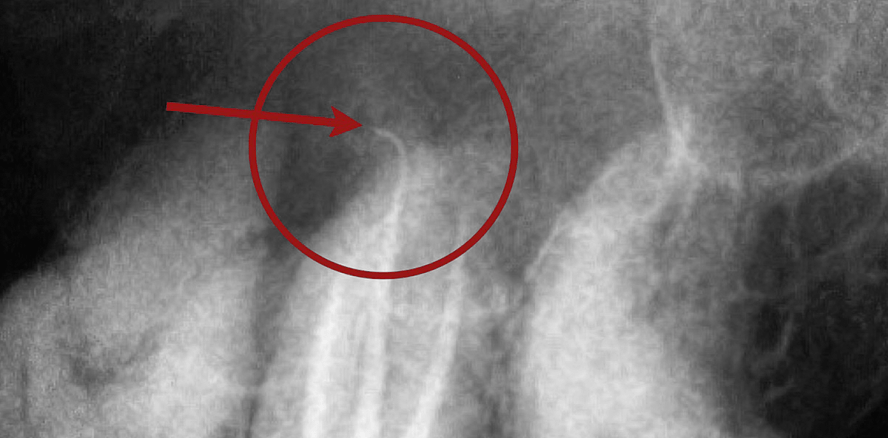

Der 67-jährige Patient stellte sich mit pulsierenden Schmerzen im rechten Unterkiefer vor. Zahn 46 war seit etwa 15 Jahren wurzelgefüllt. Das Röntgenbild zeigte, dass der Wurzelkanal nicht vollständig aufbereitet und gefüllt war (Abb. 1). Um die distalen Wurzelspitzen war eine große periapikale Veränderung sichtbar und in Form einer relativ scharf begrenzten Aufhellung zu erkennen.